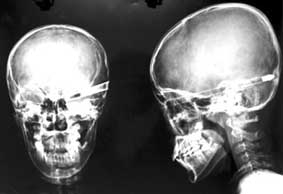

Thoát chết diệu kỳ!

-